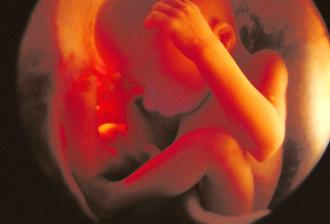

zázrak lidské života na videu

Veškeré informace jsou čerpány z internetu a to z různých stránek, proto se omlouvám, kdyby se vyskytla jakákoli nesrovnalost či chyba.